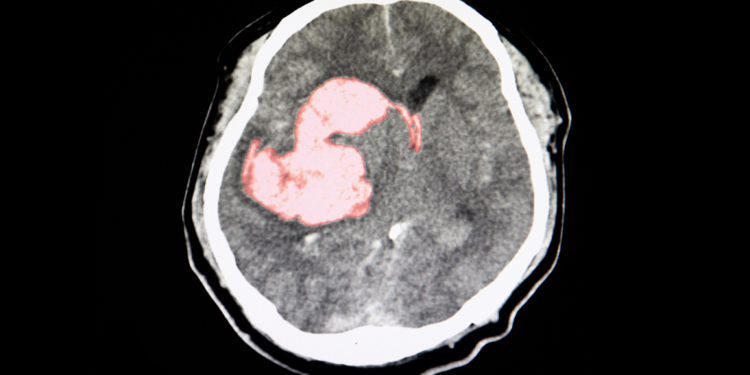

(MedPage Today) — Additional antihypertensive treatment with a three-drug polypill benefitted patients after intracerebral hemorrhage (ICH), the placebo-controlled TRIDENT trial found.